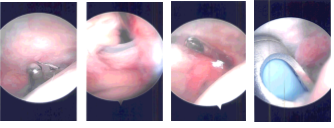

There was some fraying of the labrum, which was debrided. No rotator cuff tear could be seen on the surgical site. The Glenohumeral examination also showed inflammation of the biceps tendon with fraying. Biceps tenotomy was performed on the joint with a plan for doing a subpectoral biceps tenodesis. The scope was entered into the subacromial space.

Examination of subacromial space showed bursitis and thickened bursa, which was removed. Satisfactory acromioplasty was already there. The AC joint was intact and no inflammation was seen and so no intervention was done there.

There was superficial fraying, then 50% deep tear of the supraspinatus was seen. A decision was made to use a regeneten patch. Tear was debrided and Patch was inserted through the lateral entry portal and placed over the frayed area.

It was tacked to the rotator cuff using PLA staples x 5. The lateral part of the patch was tacked to the greater tuberosity using PEEK staples x 2. It was found to be in a stable condition. Final pictures were taken and saved.

Intraoperative Arthroscopic Images